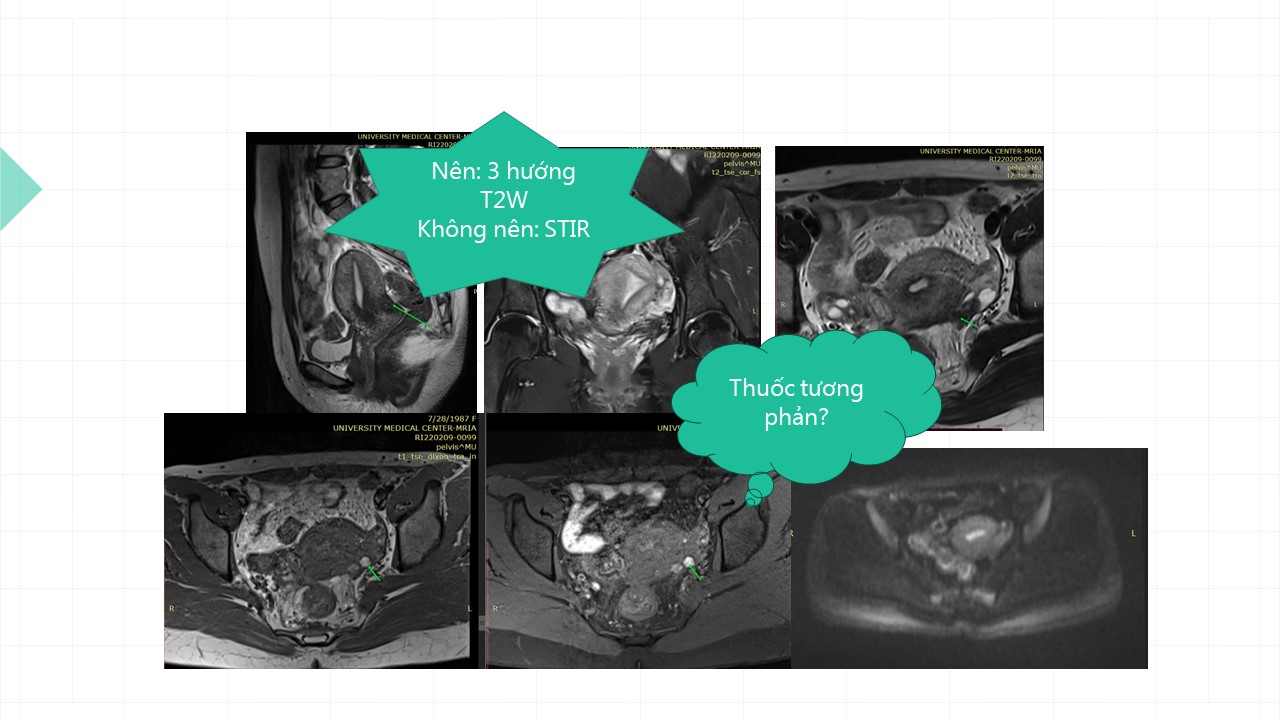

Vai trò cộng hưởng từ trong đánh giá lạc nội mạc tử cung